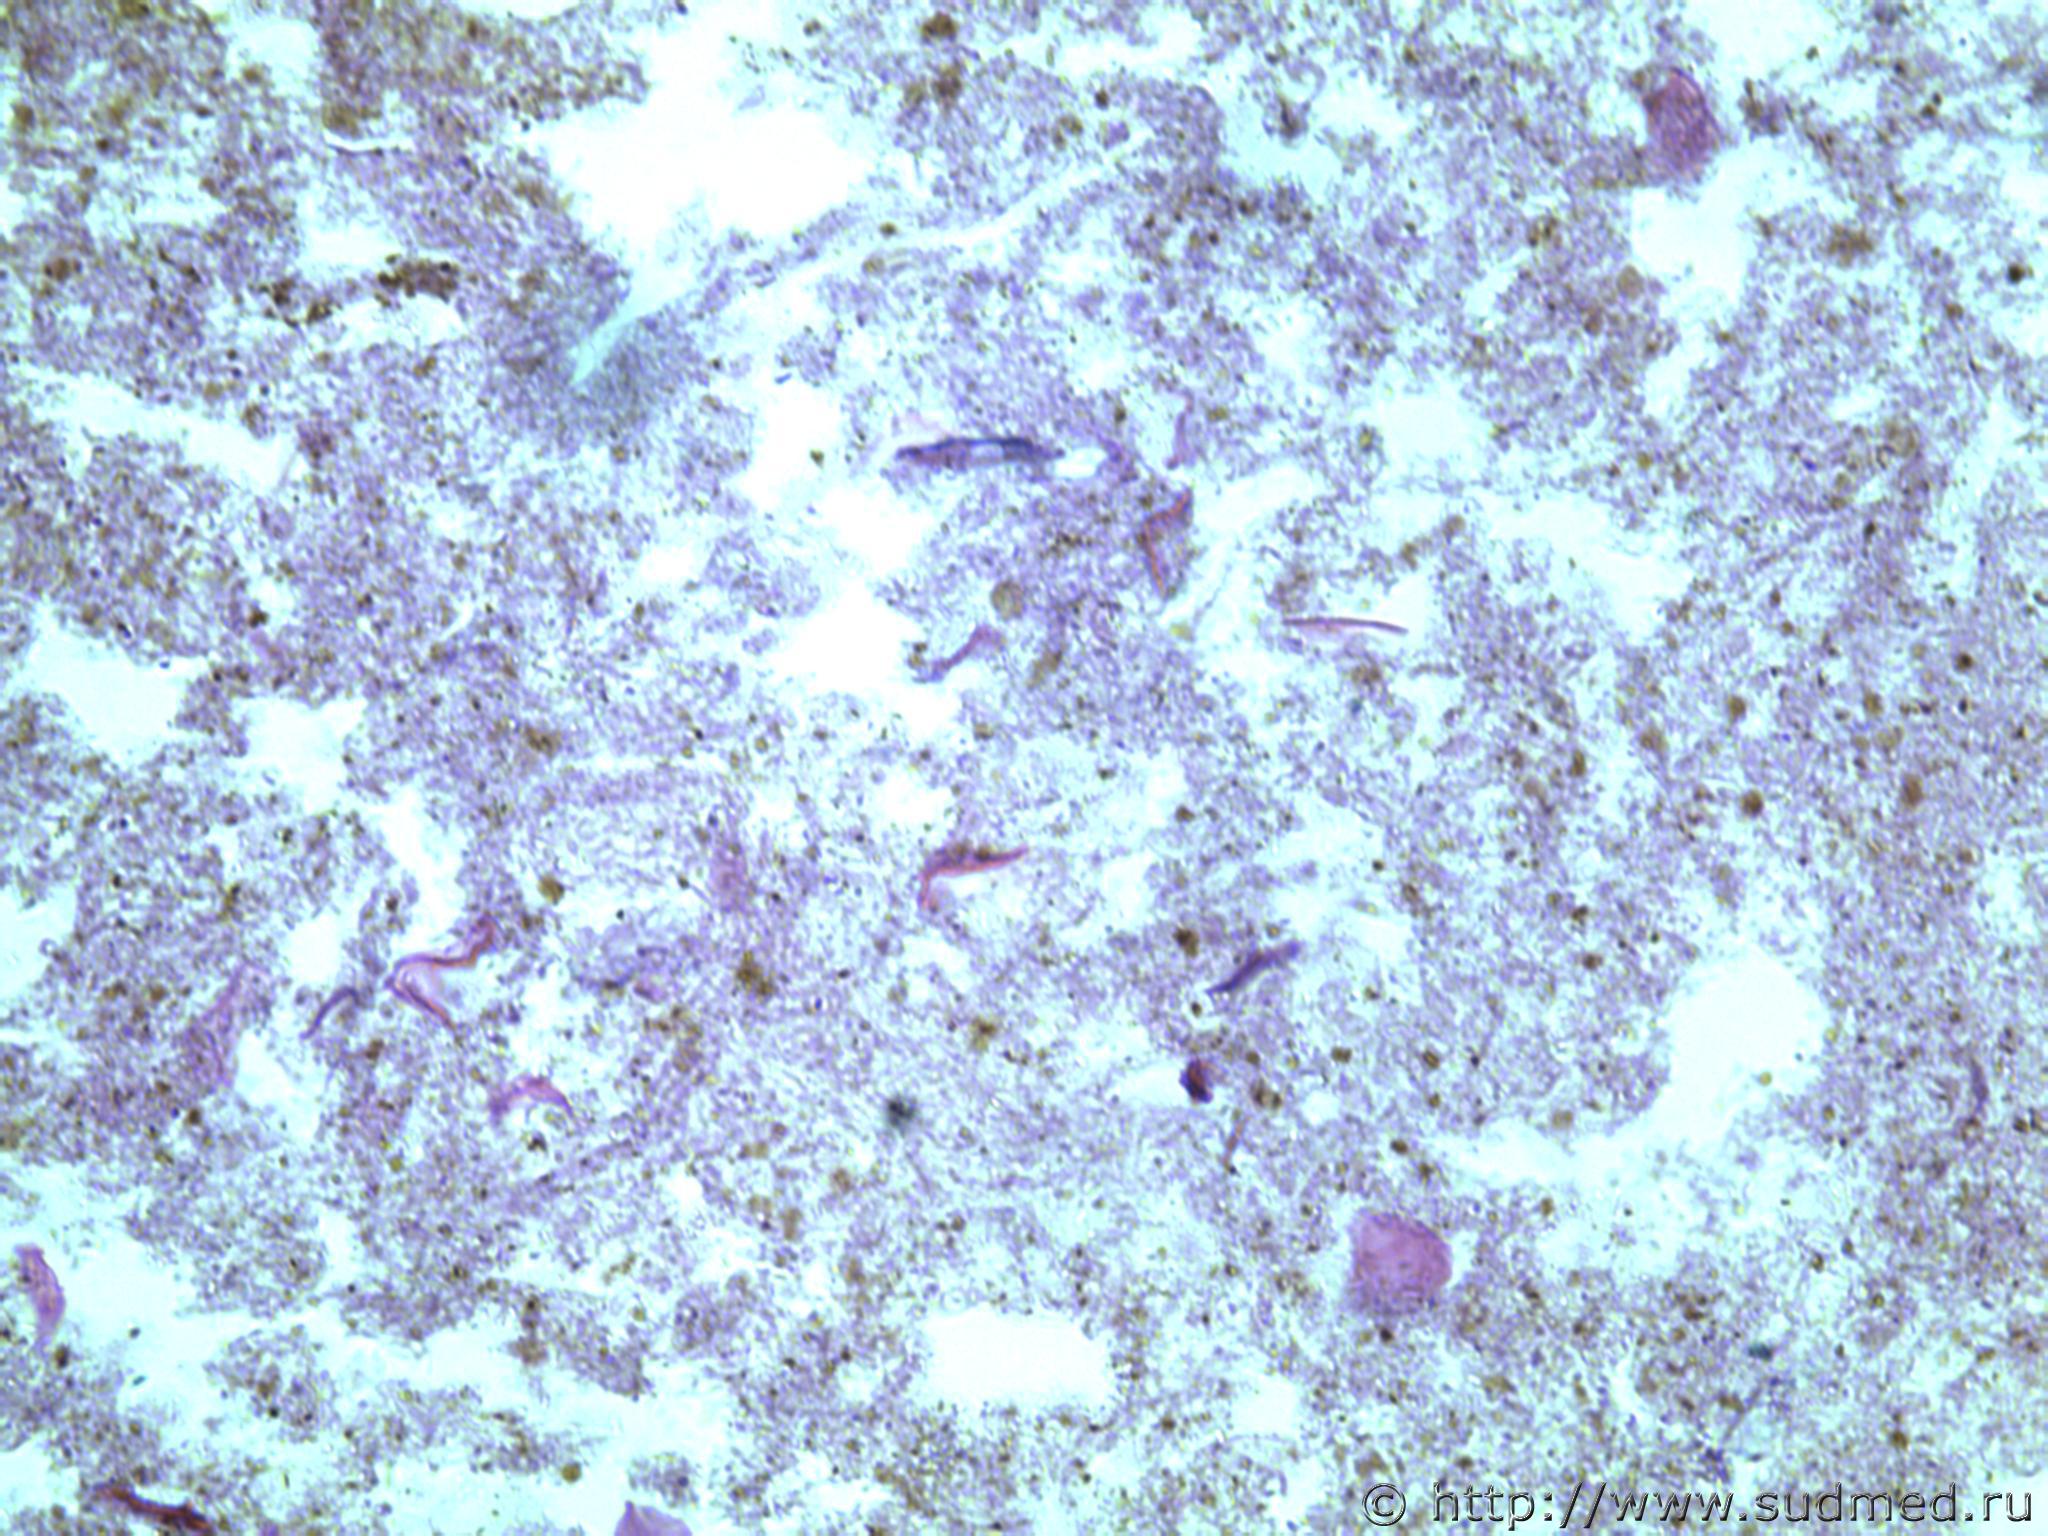

всем здравствуйте. хотела бы знать ваши мнения. провожу экспертизу. препараты как и труп новорожденного гнилые либо в аутолизе страшном. в легком картина такова, что ткань "плотная". просвет различимых альвеол в виде щелей и по всем полям зрения элементы околоплодных вод. одна артерия пуповины спазмирована. остальные сосуды непонятно : просвет их спавшийся но без признаков спазма. они как будто сплющены. да и сама пуповина в виде тонкого тяжа, видно из-за гнилостных изменений. под тмо спинного мозга признаки кровоизлияния, как и в коже с шеи. в коже головы с полнокровием отдельных сосудов. мать утверждает что ребенок после родов не сразу но все же шевелился и кричал. хотя перед этим он выпал у нее из матки на пол, ударившись головой. и со слов матери у него была пена изо рта и он хрипел.

Микрофото лёгких показать можете ?

сегодня сфоткаю конечно. но не факт что будут качественные фотки. плавательная проба - "сомнительная".

Плохо,материал гнилой.

Остановился бы на дышавшем лёгком.

В данном случае лучше вообще уйти от ответа и ограничиться фразой "в виду аутолиза и признаков универсального гниения в ткани лёгкого судить о прижизненном наличии воздуха в альвеолах не представляется возможным"

5 фото в сообщении №4 и 8 фото в сообщении №5 не наводит ли на мысль о дышавшем лёгком ?

Про остальные фото молчу,там или ничего не видно или же есть оптически пустые пузыри,что вероятнее всего,проявления гниения.